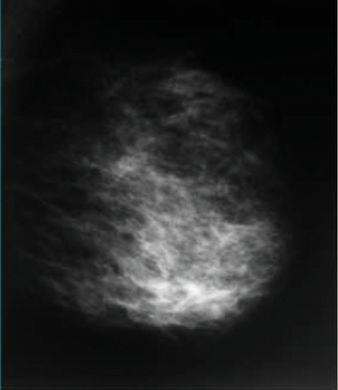

Kazuistika č.1

V DVřQ jsou tečkovité polymorfní mikrokalcifikace, ostrých kontur,

rozptýlené na ploše asi 4 cm, hodnoceny jako

semimaligní - dle histologie z biopsie prsu

invazivní duktální

karcinom